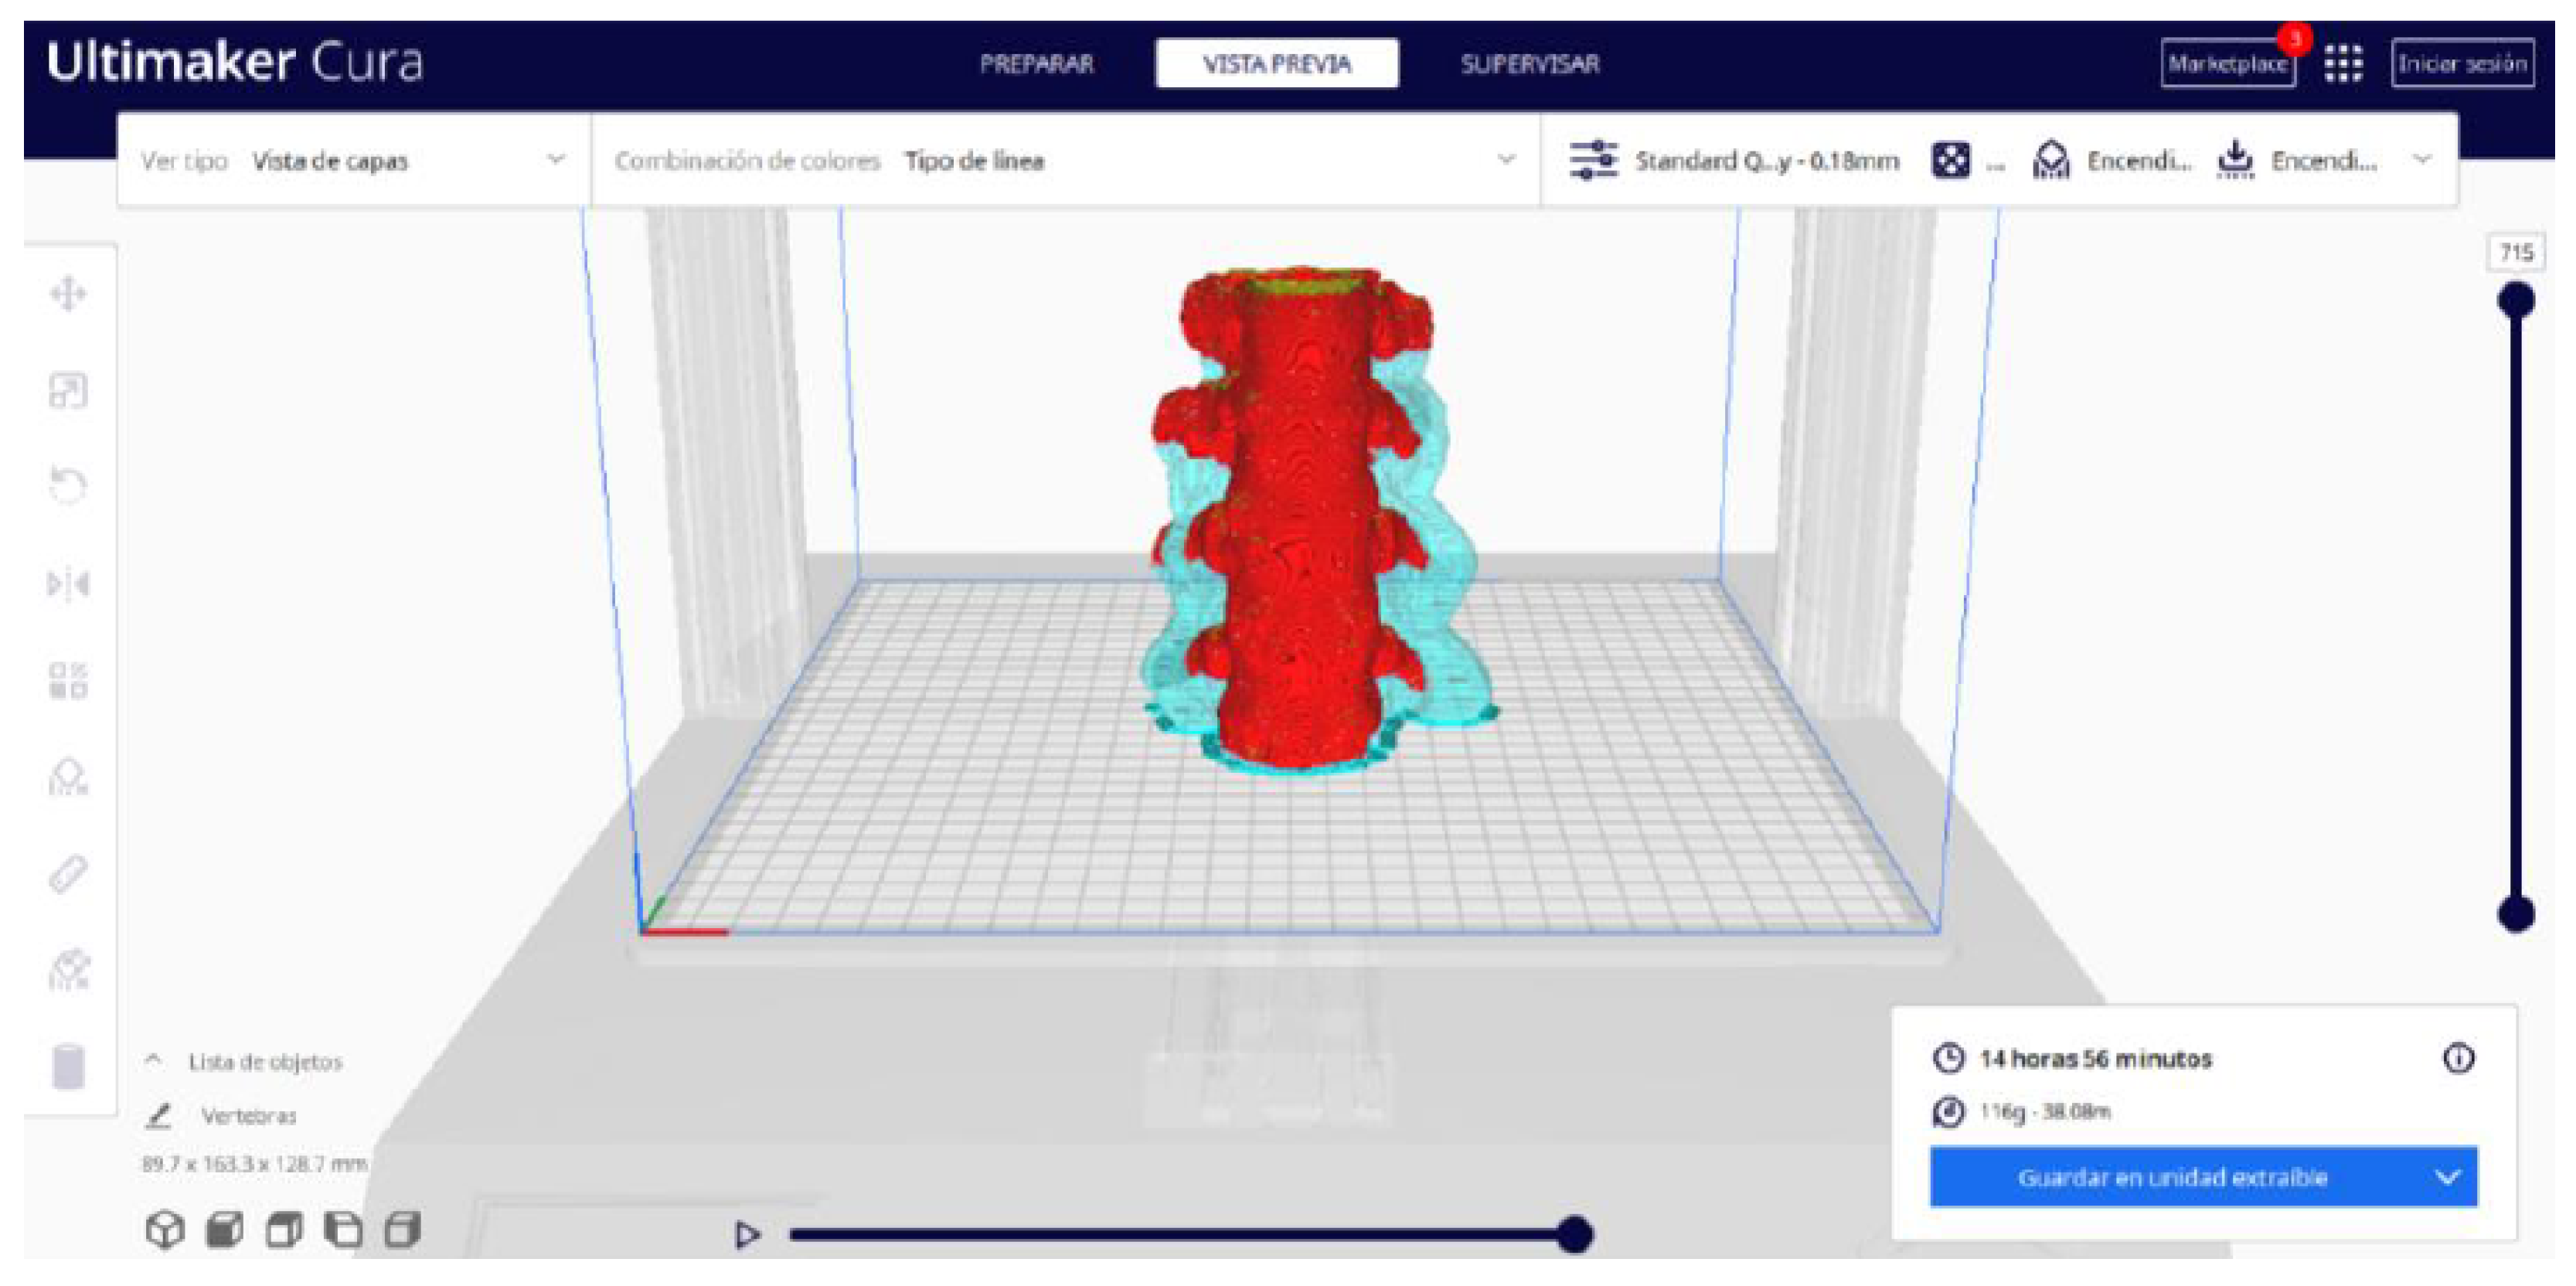

- In order to continue the STL file to GCODE conversion process, select the “Segmentation” option in Ultimaker Cura.

- The segmentation tool provides valuable information such as the estimated model weight and estimated printing time, among other crucial data.

- Once the segmentation is complete, go to the “Preview” option. Here, a sidebar will appear on the right side of the screen, giving you the ability to preview the materialisation process layer by layer, from the base to the top of the model.

- Once all the print settings are configured, select the “File” option in the Ultimaker Cura menu.

- Choose the “Export” option, and select “GCODE” as the output file type.

- Save the GCODE file to the desired location for later use in your 3D printer.

3.1.2. STL-to-GCODE File

| Vertebrae | [150, 300] | Median | 0.8 | 0.18 | 25 |

| Vertebrae models | m; m | Artillery Sidewinder X2 |